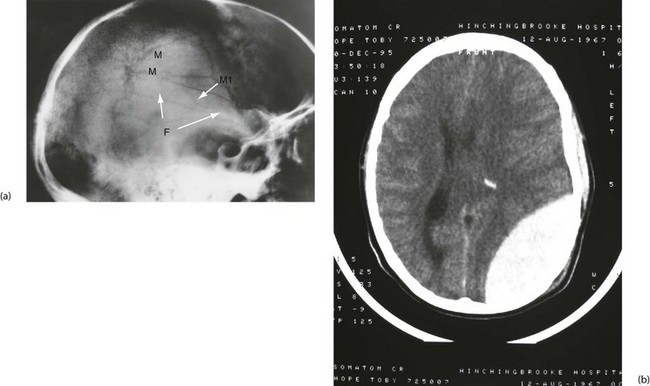

Extradural (epidural) haemorrhage: Extradural haemorrhage occurs when blood accumulates in the space between dura and calvarium. It is most common in children and younger adults, because their dura is less adherent to the skull. Most have a skull fracture, usually in the temporal region (Fig. 16.5). Almost 90% are due to rupture of an artery, usually the middle meningeal or a branch. Immediately after injury causing loss of consciousness, in up to half the patients, there will be a lucid interval, perhaps with no symptoms other than worsening headache. In either group, this is followed by deteriorating conscious level; temporal lobe herniation then leads to compression of the third nerve and pupillary dilatation. Death quickly follows unless the haematoma is evacuated rapidly. Emergency CT scanning is indicated to confirm the diagnosis (typically a lentiform-shaped clot—see Fig. 16.5b) and to show its position. With increased awareness of the condition and widespread availability of CT scanning, emergency ‘blind’ burr hole drainage is almost never appropriate. Urgent transfer to a neurosurgeon for craniotomy is the best course of action, almost without exception.